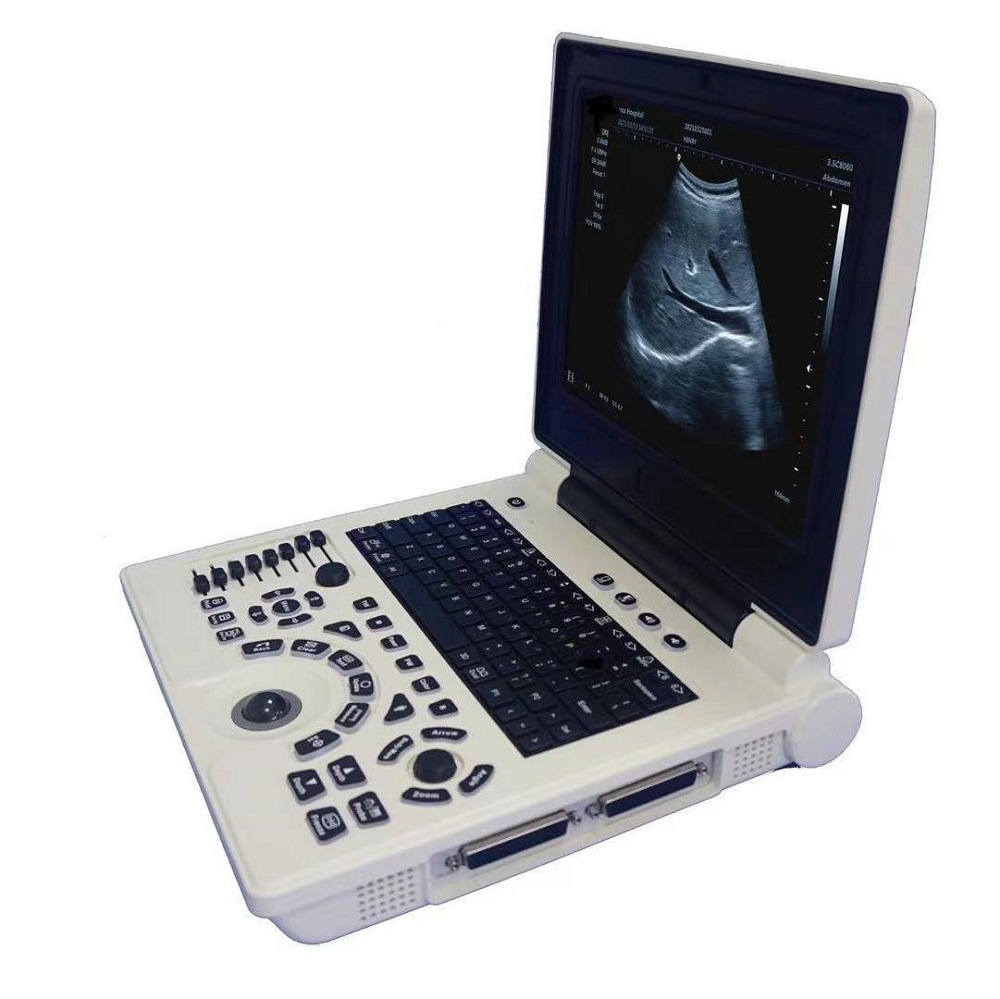

Портативный ультразвуковой аппарат Animal B; Выпуклый массивный зонд; Линейный зонд; Слегка выпуклый зонд; ректальный зонд